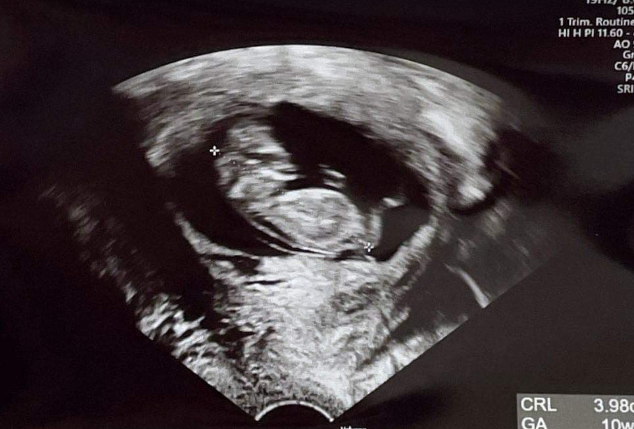

所幸在經過數周調理後,胎漏狀況已獲得改善,後經婦產科醫師超音波追蹤,在 7 周多時,有出現胎兒心音,目前胚胎持續健康發育當中,阿信醫師也持續認真幫忙養胎中,希望接下來不久,還能繼續幫媽咪做月子喔。

很開心在經過數月調理後,媽咪成功受孕,在月經推遲後媽咪自行驗孕,得知懷孕消息,這位媽咪非常慎重,還有一併至婦產科進行超音波檢查,確立胚胎著床情況,真的是替她感到開心,期待接下來龍寶寶的到來唷~。

本案媽咪,非常可愛,推測可能是先前經驗,所以一直沒有跟阿信醫師說有懷孕,在滿 8 周後,成功記錄到胎兒心音,然後居然是在孕後的 17 周後的最近,突然回診,真是讓阿信醫師又驚又喜,能讓阿信醫師一起聽到這來自天堂的聲音,真好。